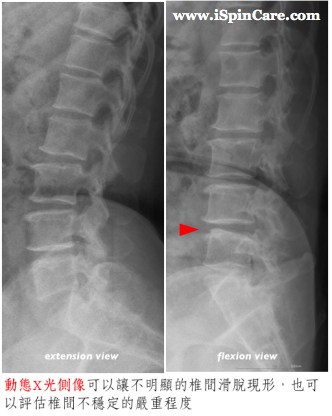

椎間滑脫由於症狀特殊,在診斷上並不困難,但若要確定診斷並評估滑脫的嚴重程度,就必須借重醫療影像,其中最簡單的莫過於X光了。最基本的腰椎X光必須包括正面和側面影像,若已知病患有所謂的「姿勢性下背痛」的話,還應該讓病患彎著腰和挺著腰各照一張動態腰椎側像的評估才算完整。滑脫嚴重程度的評估通常沿用Meyerding醫師在1947年所提出的分級標準,以下圖為例,病患的椎間滑脫程度為一度,但相當接近二度。

椎間滑脫並不一定造成脊椎的不穩定,必須比較彎腰和挺腰的動態腰椎側像,若兩者之間有明顯的差異,才能確定有脊椎的不穩定,這一點在治療建議上有著相當重要且決定性的影響。